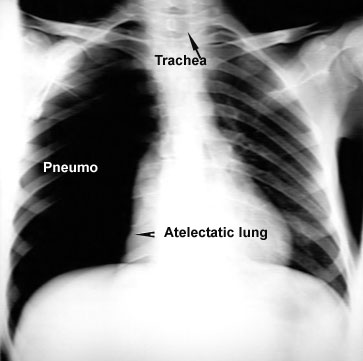

The lung is held close to chest wall because of the negative pressure in the pleural space. Once the negative pressure is lost the lung tends to recoil due to elastic properties and becomes atelectatic. This occurs in patients with pneumothorax and pleural effusion.

The following reveals a pneumothorax. In this instance, the loss of negative pressure in the pleura permits lung to relax, due to elastic recoil. There is a common misconception that atelectasis is due to compression. I disagree with that concept as is in Textbooks.